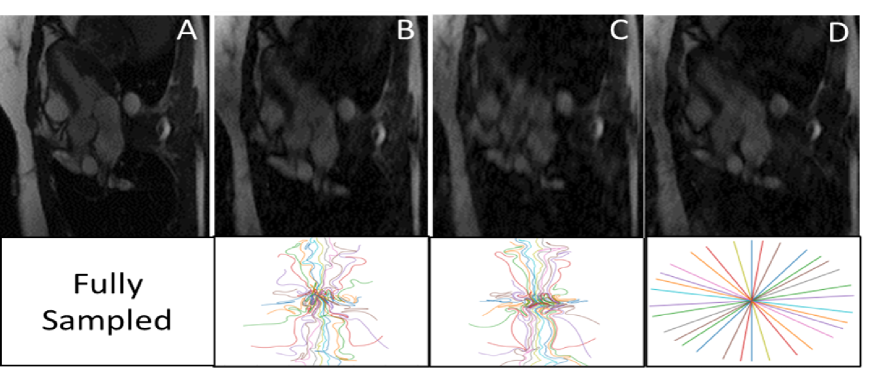

Appendix C Trajectories

In this section, we present learned trajectories using PILOT and Multi-PILOT.

In our training each data sample is consisted of 8 frames, therefore we start by initializing 8 identical radial acquisition trajectories.

Figure LABEL:fig:trajs_multi shows Multi-PILOT learns different acquisition trajectories across frames. This implies the optimal acquisition trajectories differ among frames along the temporal dimension, emphasizing the advantage of Multi-PILOT over applying static MRI pipelines in the dynamic setting.

We also present a more detailed explanation of LABEL:fig:comp.

fig:withtrajs

Figure LABEL:fig:withtrajs shows the trajectories used to acquire the corresponding frames from LABEL:fig:comp. Many of the data in each frame is encapsulated at the center of the -space. The learned trajectories show that while PILOT’s single trajectory must allocate many acquisition points for capturing central frequencies, the Multi-PILOT trajectory can afford using trajectories more spread around the -space, as data represented using the center frequencies are also captured by other frames. MultiPILOT does better in reconstructing the finer details compared to GAR initialization and PILOT reconstruction.